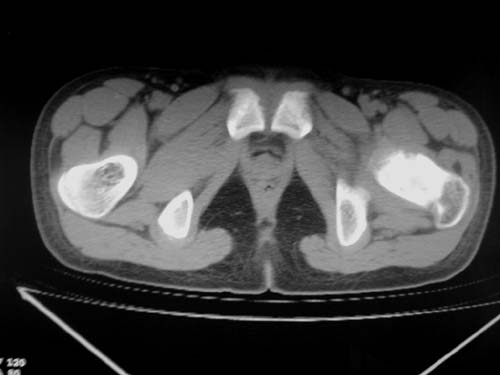

标题: CT19608:女12岁,左髋部疼痛,无发热病史 [打印本页]

标题: CT19608:女12岁,左髋部疼痛,无发热病史

左股骨干增粗,磨玻璃样改变——考虑骨纤维异常增殖症!

左股骨干增粗,磨玻璃样改变——考虑骨纤维异常增殖症!骨化性纤维瘤?